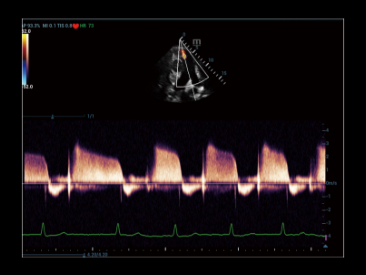

Una nueva forma de demostrar el Color/flujo Doppler de potencia 2D de forma innovadora en una visualizaciĂłn 3D

Caso con Glazing Flow (modo de potencia):

?rbol de la arteria renal.

Glazing Flow ofrece una visualizaciĂłn nĂtida de las arterias arciformes y la estructura de la arteria interlobular menor con visualizaciĂłn en 3D.